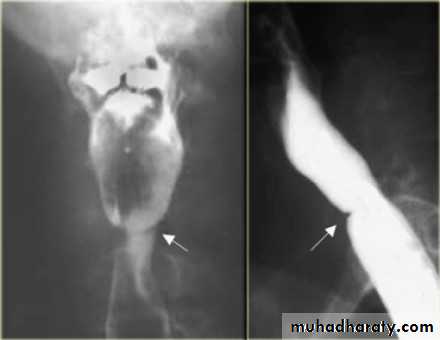

Webs

Majority protrude from anterior esophageal wall

short, thin web (arrows) with minimal intraluminal extension.